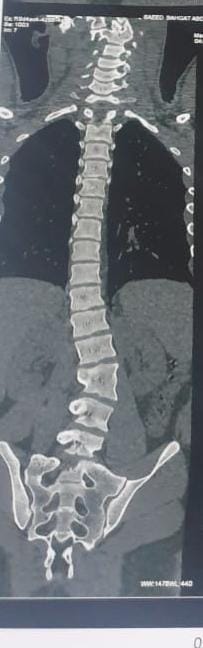

وأضاف مدكور أنه جرى استقبال المريض وهو يعانى من الالام شديدة بالظهر مع عدم الاستجابه للعلاج الدوائي والعلاج الطبيعى وعقب الفحص تبين وجود اعوجاج بالفقرات الصدريه والقطنيه بالعمود الفقري.

فيما أوضح الدكتور احمد البيلى وكيل المديرية للطب العلاجى أنه عقب مناظرة الاشعة والفحوصات تم إجراء العملية التى استغرقت 4 ساعات كاملة لإصلاح الاعوجاج بواسطه تثبيت الفقرات الصدريه والقطنيه واستعدال العمود الفقرى مع خروج المريض من المستشفى وتحسن حالته.